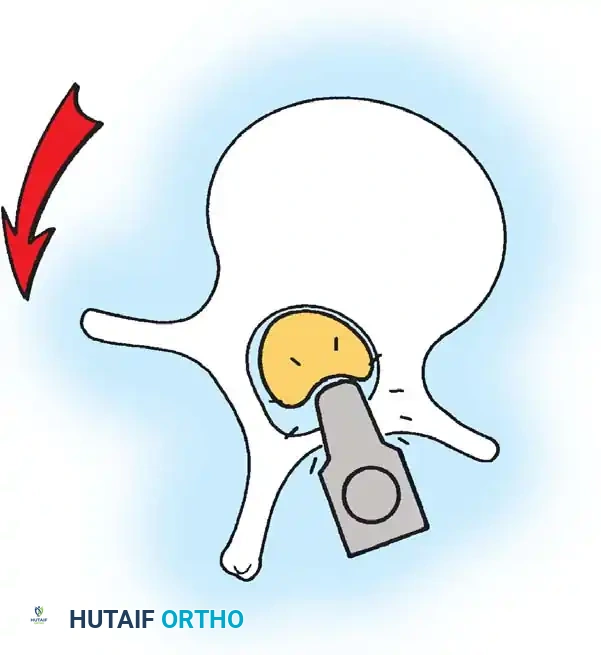

The Moe Technique (Thoracic Spine)

The Moe technique is a highly effective method for achieving intra-articular arthrodesis in the coronally oriented thoracic facet joints.

Fig. 38-26: The Moe technique of thoracic facet fusion, demonstrating the creation of hinged bone flaps.

- Expose the spine fully to the tips of the transverse processes.

- Using a sharp osteotome or Cobb gouge, begin a cut over the cephalad articular process at the base of the lamina.

- Carry this cut along the transverse process almost to its tip. Bend this cortical fragment laterally so it lies between the transverse processes, ideally leaving it hinged on its lateral periosteal attachment to preserve local vascularity.

- Thoroughly denude all articular cartilage from the superior articular process using a sharp curet.

- Make a secondary cut in the superior articular facet, working medially to laterally, producing another hinged fragment.

- Pack the resulting intra-articular defect tightly with cancellous bone graft.